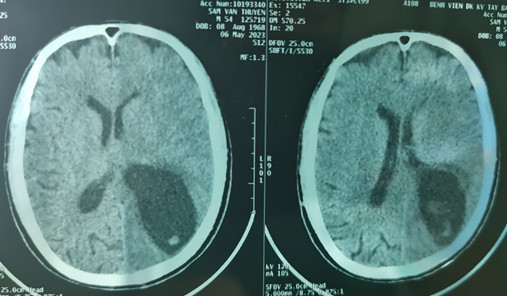

| Phim chụp cắt lớp vi tính sọ não trước khi phẫu thuật - Ảnh: BV Hữu nghị đa khoa Nghệ An |

Sau khi vào Bệnh Viện đa khoa Tây Bắc (Nghệ An) được các y bác sĩ thăm khám cho kết quả xét nghiệm phân tìm ký sinh trùng (+), xét nghiệm ELISA chẩn đoán ấu trùng sán lợn Cysticercosis(+), chụp cắt lớp vi tính não cho thấy có nhiều ổ ổ giảm tỷ trọng kèm phù não lớn vùng bán cầu trái. Kết luận cho rằng bệnh nhân bị Hội chứng tăng áp lực nội sọ do ấu trùng sán dây lợn trên hệ thần kinh, nguy cơ tử vong cao nếu không xử lý kịp thời.